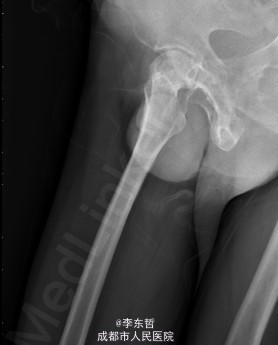

患者男,62岁,因“双髋疼痛4年,加重伴活动受限1年”入院。病员诉入院前4年无明显诱因出现双侧髋部疼痛,行走后疼痛加重,疼痛能忍受,双侧髋部无红肿,皮温不高,无畏寒、发热,休息后疼痛能自行缓解,无夜间疼痛,在当地医院行止痛药内服、理疗治疗,疼痛稍缓解。逐渐加重,1年前双侧髋部疼痛、跛行明显加重,左髋活动受限,行走困难,给予对症治疗症状无明显改善,遂到我科门诊就诊,X线片提示:双侧股骨头坏死,建议手术治疗,故于今日以“双侧侧股骨头坏死”收入我科进一步治疗。

查体:生命体征平稳,心肺腹未见异常;跛行,双左下肢较右下肢短缩1cm,左、右腹股沟中点深压痛,左、右髋叩击痛,左髋屈20°,伸0°,外展10°,内收10°,右髋屈60°,伸0°,外展20°,内收20°。双髋内、外旋活动受限,诱发疼痛,左侧重。 辅助检查:x线片示双侧股骨头坏死、塌陷变形,左侧明显,左髋半脱位。

初步诊断:1、左侧股骨头坏死伴内收肌挛缩(Ficat IV期);2、右侧股骨头坏死(Ficat IV期);3、右膝骨关节炎伴外翻畸形;入院后积极完善术前检查及准备,择期行手术治疗。